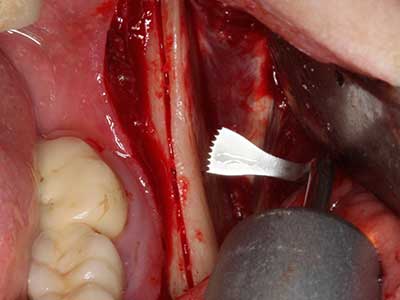

Sollen chirurgische Eingriffe mit unmittelbarer Knochenbeziehung an empfindlichen Strukturen wie Blutgefäßen oder Nerven erfolgen, so bergen rotierende Instrumente ein erhebliches Potential an iatrogener Schädigung. Gerade bei Nervdarstellungen nach iatrogener Schädigung, oder aber im Zuge einer Nervlateralisation für resektive und rekonstruktive Eingriffe oder Implantatinsertionen können piezoelektronische Geräte hilfreich sein Knochendeckel zu präparieren und nervnahe Hartgewebsanteile zu entfernen (Abb. 17-20). Ein leichter Kontakt des Nervstrangs zur Piezospitze bleibt dabei in der Regel folgenlos – allerdings kann eine unvorsichtige Vorgehensweise mit sägeartigen Bewegungen bzw. Ansätzen bei noch vorhandener knöcherner Unterlage durchaus temporäre oder aber auch permanente Nervschädigungen verursachen. Das Risiko einer solchen Schädigung wird jedoch als wesentliche geringer eingeschätzt als unter Anwendung von Säge- oder Fräsinstrumenten (Pereira, Gealh et al. 2014).

Indikation: Parodontaltherapie